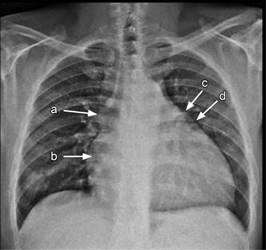

A la exploración física encontramos los siguientes datos de importancia: peso de 88 kg, talla de 166 cm, IMC igual a 32; TA: 100/80, FC: 1.10 latidos/min; FR: 18 r/min; saturación O2 74% al aire ambiental y temperatura de 38.1 oC. Se observó plétora yugular e hipocratismo digital; precordio hiperdinámico, con ruidos cardiacos rítmicos, presencia de soplo sistólico tricuspídeo III/VI; segundo P apagado, y campos pulmonares limpios con murmullo vesicular normal. El abdomen se encontraba con hepatomegalia no dolorosa de 1 cm por debajo del borde costal. Se encontraron pulsos presentes en las cuatro extremidades y sin edema. La radiografía tele de tórax mostró cardiomegalia global con dilatación de aurícula derecha e hipertrofia ventricular derecha, abombamiento del arco pulmonar y signo de hachazo (Figura 1).

Figura 1: Radiografía tele de tórax que evidencia cardiomegalia global con dilatación de aurícula (a) e hipertrofia del ventrículo derecho (b), abombamiento del arco pulmonar (c) y signo del hachazo (d) (flechas).